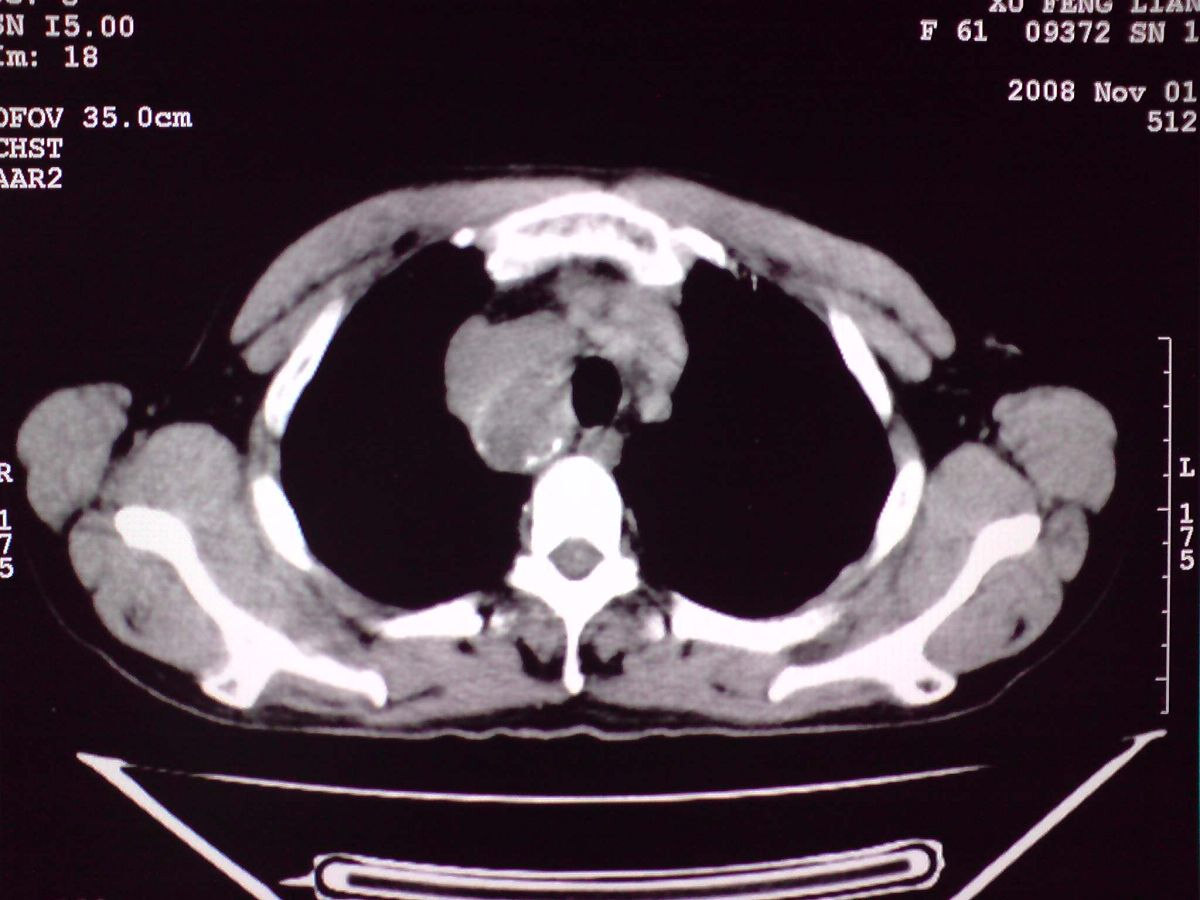

患者女性,65岁,无明显不适,甲状腺功能无异常

结节状甲状腺肿,部分突入胸腔,形成胸内甲状腺

胸内甲状腺伴结节性甲状腺肿!因病灶明显钙化很难排除:甲状腺癌可能性!建议穿刺活检!

双侧甲状腺肿大,向下部分突入胸腔,双侧甲状腺内密度不均,可见结节状低密度影,并见散在斑点状钙化,增强后病灶实性部分强化明显,气管受压稍变窄左移。

考虑:双侧甲状腺腺瘤可能,不除外甲状腺癌。

甲状腺左右叶增大,并向下突入胸腔内,其内可见多发条片状钙化影及囊性低密度影,邻近组织及血管无浸润、包埋征像,双侧结节性甲状腺肿伴右侧甲状腺腺瘤形成可能性大,甲状腺癌待排;因病人就要手术,期待结果。